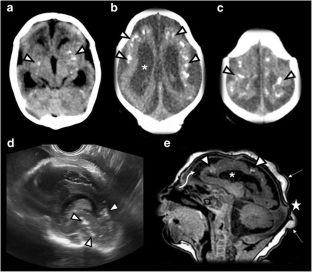

Fig. 1

Fig. 2

Fig. 3

Fig. 4

Fig. 5